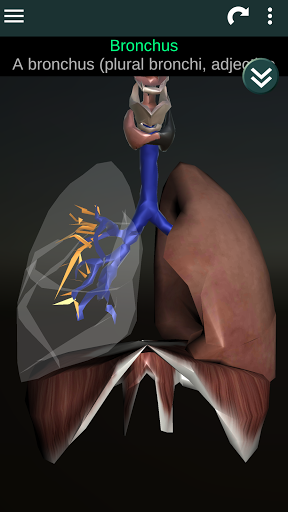

Shows a 3D anatomical model of the main organs of the human body and a description of each one.

* Respiratory system, which includes the trachea, bronchi, lungs and an animation of this system.

* Easy to access and navigate (zoom, 3D rotation).

* Descriptions of each organ.